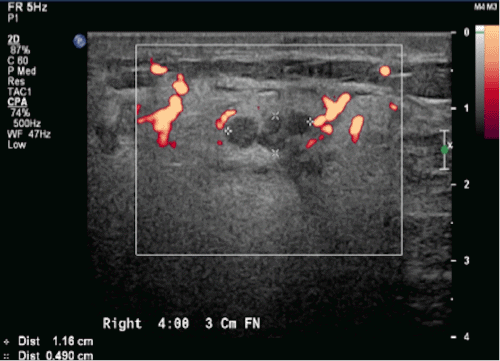

Over the next six months, the patient reported enlargement of the mass and slight tenderness. A right breast ultrasound was suggestive of a 1.5 cm fibroadenoma. One month later, a diagnostic mammogram demonstrated diffusely increased parenchymal density and skin thickening but no dominant mass. Repeat ultrasound demonstrated a 5 cm hyperechoic area with a 1.2 cm central area of hypoechogenicity, a series of nodules, and "intense surrounding blood flow" (Figure 1). Core needle biopsy revealed a vasoformative lesion, favoring a hemangioma. In the operative note of the subsequent excisional biopsy, "extremely large vessels circumferentially around the mass" were noted. After a pathologic review locally and at a tertiary academic medical center, the final diagnosis was a well-differentiated angiosarcoma of the breast, which measured 1.2 cm by gross examination. Although the surgical margins were not specifically addressed, completion mastectomy was recommended.

Figure 1. Targeted Ultrasound of Right Breast Taken before Biopsy. Published with Permission

A) Hyperechoic mass with nodules within breast parenchyma

B) Blood flow within and surrounding mass